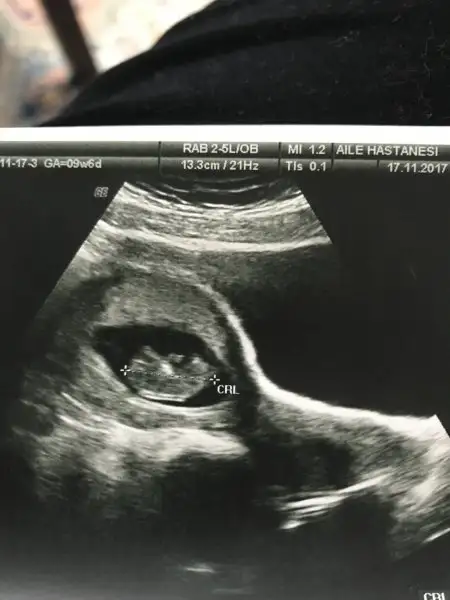

Daha bebek olusmamistir senin.Canım 7 haftalık olsun ancak yorum yapılabilir.8 hafta olsa olmaz mesela çünkü bebek hareket ediyor rahim içinde yer değiştirebiliyor.Canım benim kesede tam ortada görünüyor. Yeni olduğu için galiba di mi

Canım kese yorumu için 7 haftalık ultrason görüntüsü lazımEki Görüntüle 2068715 Kızlar benimkinide yorumlarmısınız?

9+6 fazla mi oluyoCanım kese yorumu için 7 haftalık ultrason görüntüsü lazım

Evet canım 8.haftadan sonra bebek hareket edebiliyor rahim içerisinde ve bu yüzden yapılan tahminin tutma orani da azaliyor9+6 fazla mi oluyo